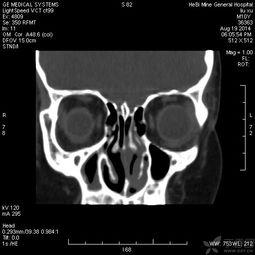

2. 定位:医生会使用影像学设备,如CT或MRI,来确定鼻窦的位置和脓液积聚的具体位置。